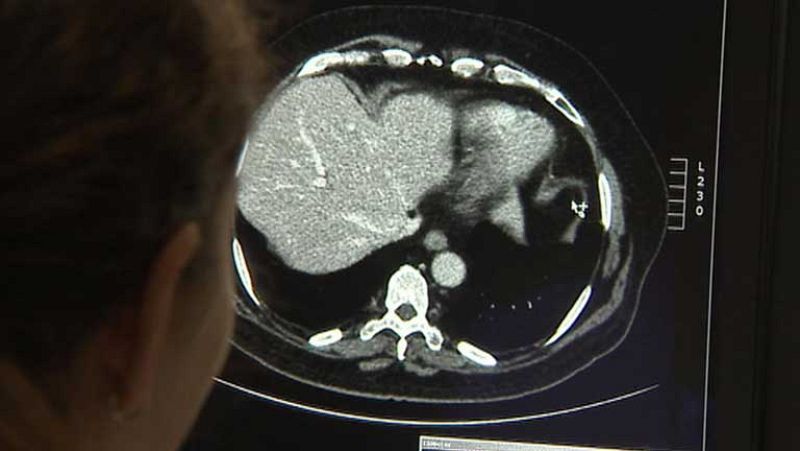

Hoy es el día internacional de la radiología; una rama médica con poca visibilidad entre los pacientes pero fundamental en la prevención y diagnóstico de muchas enfermedades. Ha reducido la mortalidad del cáncer de mama un 30%, un 20% el de pulmón en fumadores. Lo último es la detección precoz y el tratamiento de tumores abdominales.